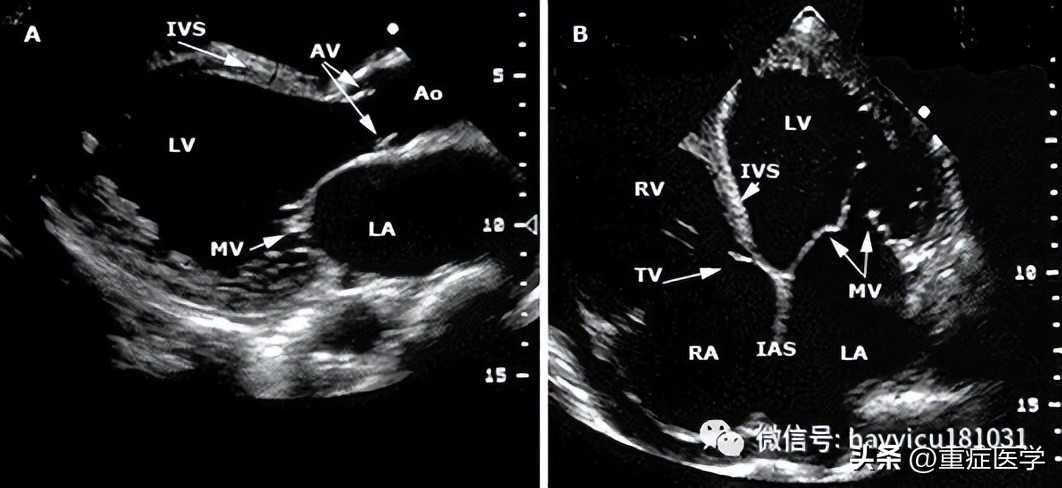

即时超声—POC超声的流程包括休克患者快速超声检查(rapid ultrasound in shock, RUSH)、重点心脏超声(focused cardiac ultrasound, FOCUS)以及休克患者腹部和心脏超声评估(abdominal and cardiac evaluation with sonography in shock, ACES),更常用作不明原因休克和低血压患者的便携式床旁诊断工具。当条件允许时,POC超声通常用于经临床和实验室评估未做出经验性诊断的患者,或进行确定性影像学检查不安全的患者(流程图 1A-B),也用作检查补液效果的辅助工具。虽然POC超声不能确定诊断,但我们认为,当由受过培训人员对有不明原因休克或低血压的危重患者将其作为时效性诊断工具使用时,可获得能挽救生命的有价值信息。多器官超声(RUSH、ACES)首先检查心脏,之后检查胸部、腹部和大血管;FOCUS仅检查心脏。不明原因的休克患者中POC超声采用的技术视图与在创伤患者中使用的(FAST)类似,将单独详细讨论。POC超声检查的组成将在下文简单介绍:首先,应该实施有限视图的心脏检查,查看下列部位:心包–心脏超声可能发现心包积液(无回声带);心腔塌陷,以及呼吸过程中右心室和左心室容积呈相反变化支持心包填塞为休克原因。心脏超声也可用于引导心包穿刺和检查引流效果。左心室–左心室偏大伴收缩力降低可能提示原发性泵衰竭,需要安排适当的干预(如心导管术)。相反,心腔较小和左室高动力可能提示脓毒症导致的分布性休克或血容量不足,分别需要进一步评估脓毒症来源或评估出血。左心室成像也可用于确定安置起搏器(经皮或经静脉)引起的心室收缩或室壁穿孔,或动脉瘤破裂。右心室–右心室收缩力降低可能提示右室心肌梗死;右心室扩大(如,右心室/左心室体积>1:1)可能提示大型肺栓塞或肺动脉高压;右心房/右心室中漂浮的血栓或移动的血凝块也支持肺栓塞。下腔静脉–呼气末下腔静脉(inferior vena cava, IVC)塌陷提示失血性或非失血性原因导致的血容量不足。下腔静脉扩张可能支持心包填塞或肺栓塞。第二,应对胸部和腹部进行简明成像来检查下列部位:肺和胸膜腔–无肺滑行征(视频 5)支持气胸的存在。肺水肿(证据为存在B线)可能支持原发性泵衰竭或继发于液体复苏的容量超负荷。胸膜腔积液(无回声带或分隔)支持脓胸或血胸,并可指导胸膜腔穿刺。腹膜腔–腹膜腔中有大量液体积聚的证据可提示创伤的出血源,或感染的潜在来源(即,肝硬化患者的自发性细菌性腹膜炎)。第三,应对大动脉和静脉进行简明成像以检查下列部位:主动脉–虽然首选胸部CT或经食管超声心动图,但POC超声可发现胸部或腹部动脉瘤或与主动脉夹层相符的内膜瓣。另外,查见游离液体、心包积液或胸膜腔积液也可作为动脉瘤破裂或动脉夹层的间接证据。近端下肢静脉–股静脉缺乏可压缩性可能提示深静脉血栓形成,从而提示临床医生怀疑肺栓塞。如果POC超声不具诊断意义或无法进行,只要条件允许应该进行确定性影像学检查,其中综合性超声心动图最有帮助。同样,如果从休克中成功复苏,采用标准影像学进行后续检查以证实通过快速床旁超声获得的诊断也是明智的。在不明原因的休克患者中,POC超声的优缺点包括: